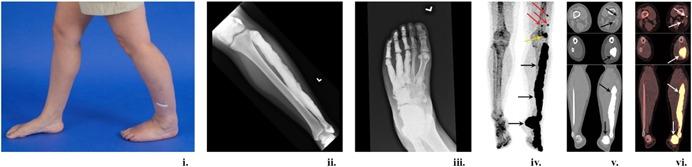

Melorheostosis is a rare dysostosis involving cortical bone overgrowth that affects the appendicular skeleton. Patients present with pain, deformities, contractures, range of motion limitation(s), and limb swelling. It has been described in children as well as adults. We recently identified somatic mosaicism for gain-of-function mutations in in patients with melorheostosis. Despite these advances in genetic understanding, there are no effective therapies or clinical guidelines to help clinicians and patients in disease management. In a study to better characterize the clinical and genetic aspects of the disease, we recruited 30 adults with a radiographic appearance of melorheostosis and corresponding increased uptake on F-NaF positron emission tomography (PET)/CT. Patients underwent physical exam, imaging studies, and laboratory assessment. All patients underwent nerve conduction studies and ultrasound imaging of the nerve in the anatomic distribution of melorheostosis. We found sensory deficits in approximately 77% of patients, with evidence of focal nerve entrapment in five patients. All patients reported pain; 53% of patients had changes in skin overlying the affected bone. No significant laboratory abnormalities were noted. Our findings suggest that patients with melorheostosis may benefit from a multidisciplinary team of dermatologists, neurologists, orthopedic surgeons, pain and palliative care specialists, and physical medicine and rehabilitation specialists. Future studies focused on disease management are needed. © 2019 The Authors. Published by Wiley Periodicals, Inc. on behalf of American Society for Bone and Mineral Research.

肢骨纹状肥大是一种罕见的骨发育异常,累及皮质骨过度生长,影响四肢骨骼。患者表现为疼痛、畸形、挛缩、活动范围受限和肢体肿胀。儿童及成人中均有该病的描述。我们最近在肢骨纹状肥大患者中发现了功能获得性突变的体细胞镶嵌现象。尽管在遗传学认识方面取得了这些进展,但仍没有有效的治疗方法或临床指南来帮助临床医生和患者进行疾病管理。在一项旨在更好地描述该病临床和遗传特征的研究中,我们招募了30名具有肢骨纹状肥大影像学表现且在氟代钠正电子发射断层扫描(PET)/CT上相应摄取增加的成年人。患者接受了体格检查、影像学检查和实验室评估。所有患者均进行了神经传导研究以及肢骨纹状肥大解剖分布区域神经的超声成像检查。我们发现约77%的患者存在感觉缺陷,5名患者有局灶性神经卡压的证据。所有患者均报告有疼痛;53%的患者受累骨骼上方皮肤有改变。未发现明显的实验室异常。我们的研究结果表明,肢骨纹状肥大患者可能受益于皮肤科医生、神经科医生、骨科医生、疼痛与姑息治疗专家以及物理医学与康复专家组成的多学科团队。需要开展针对疾病管理的未来研究。© 2019作者。由威利期刊公司代表美国骨与矿物质研究学会出版。